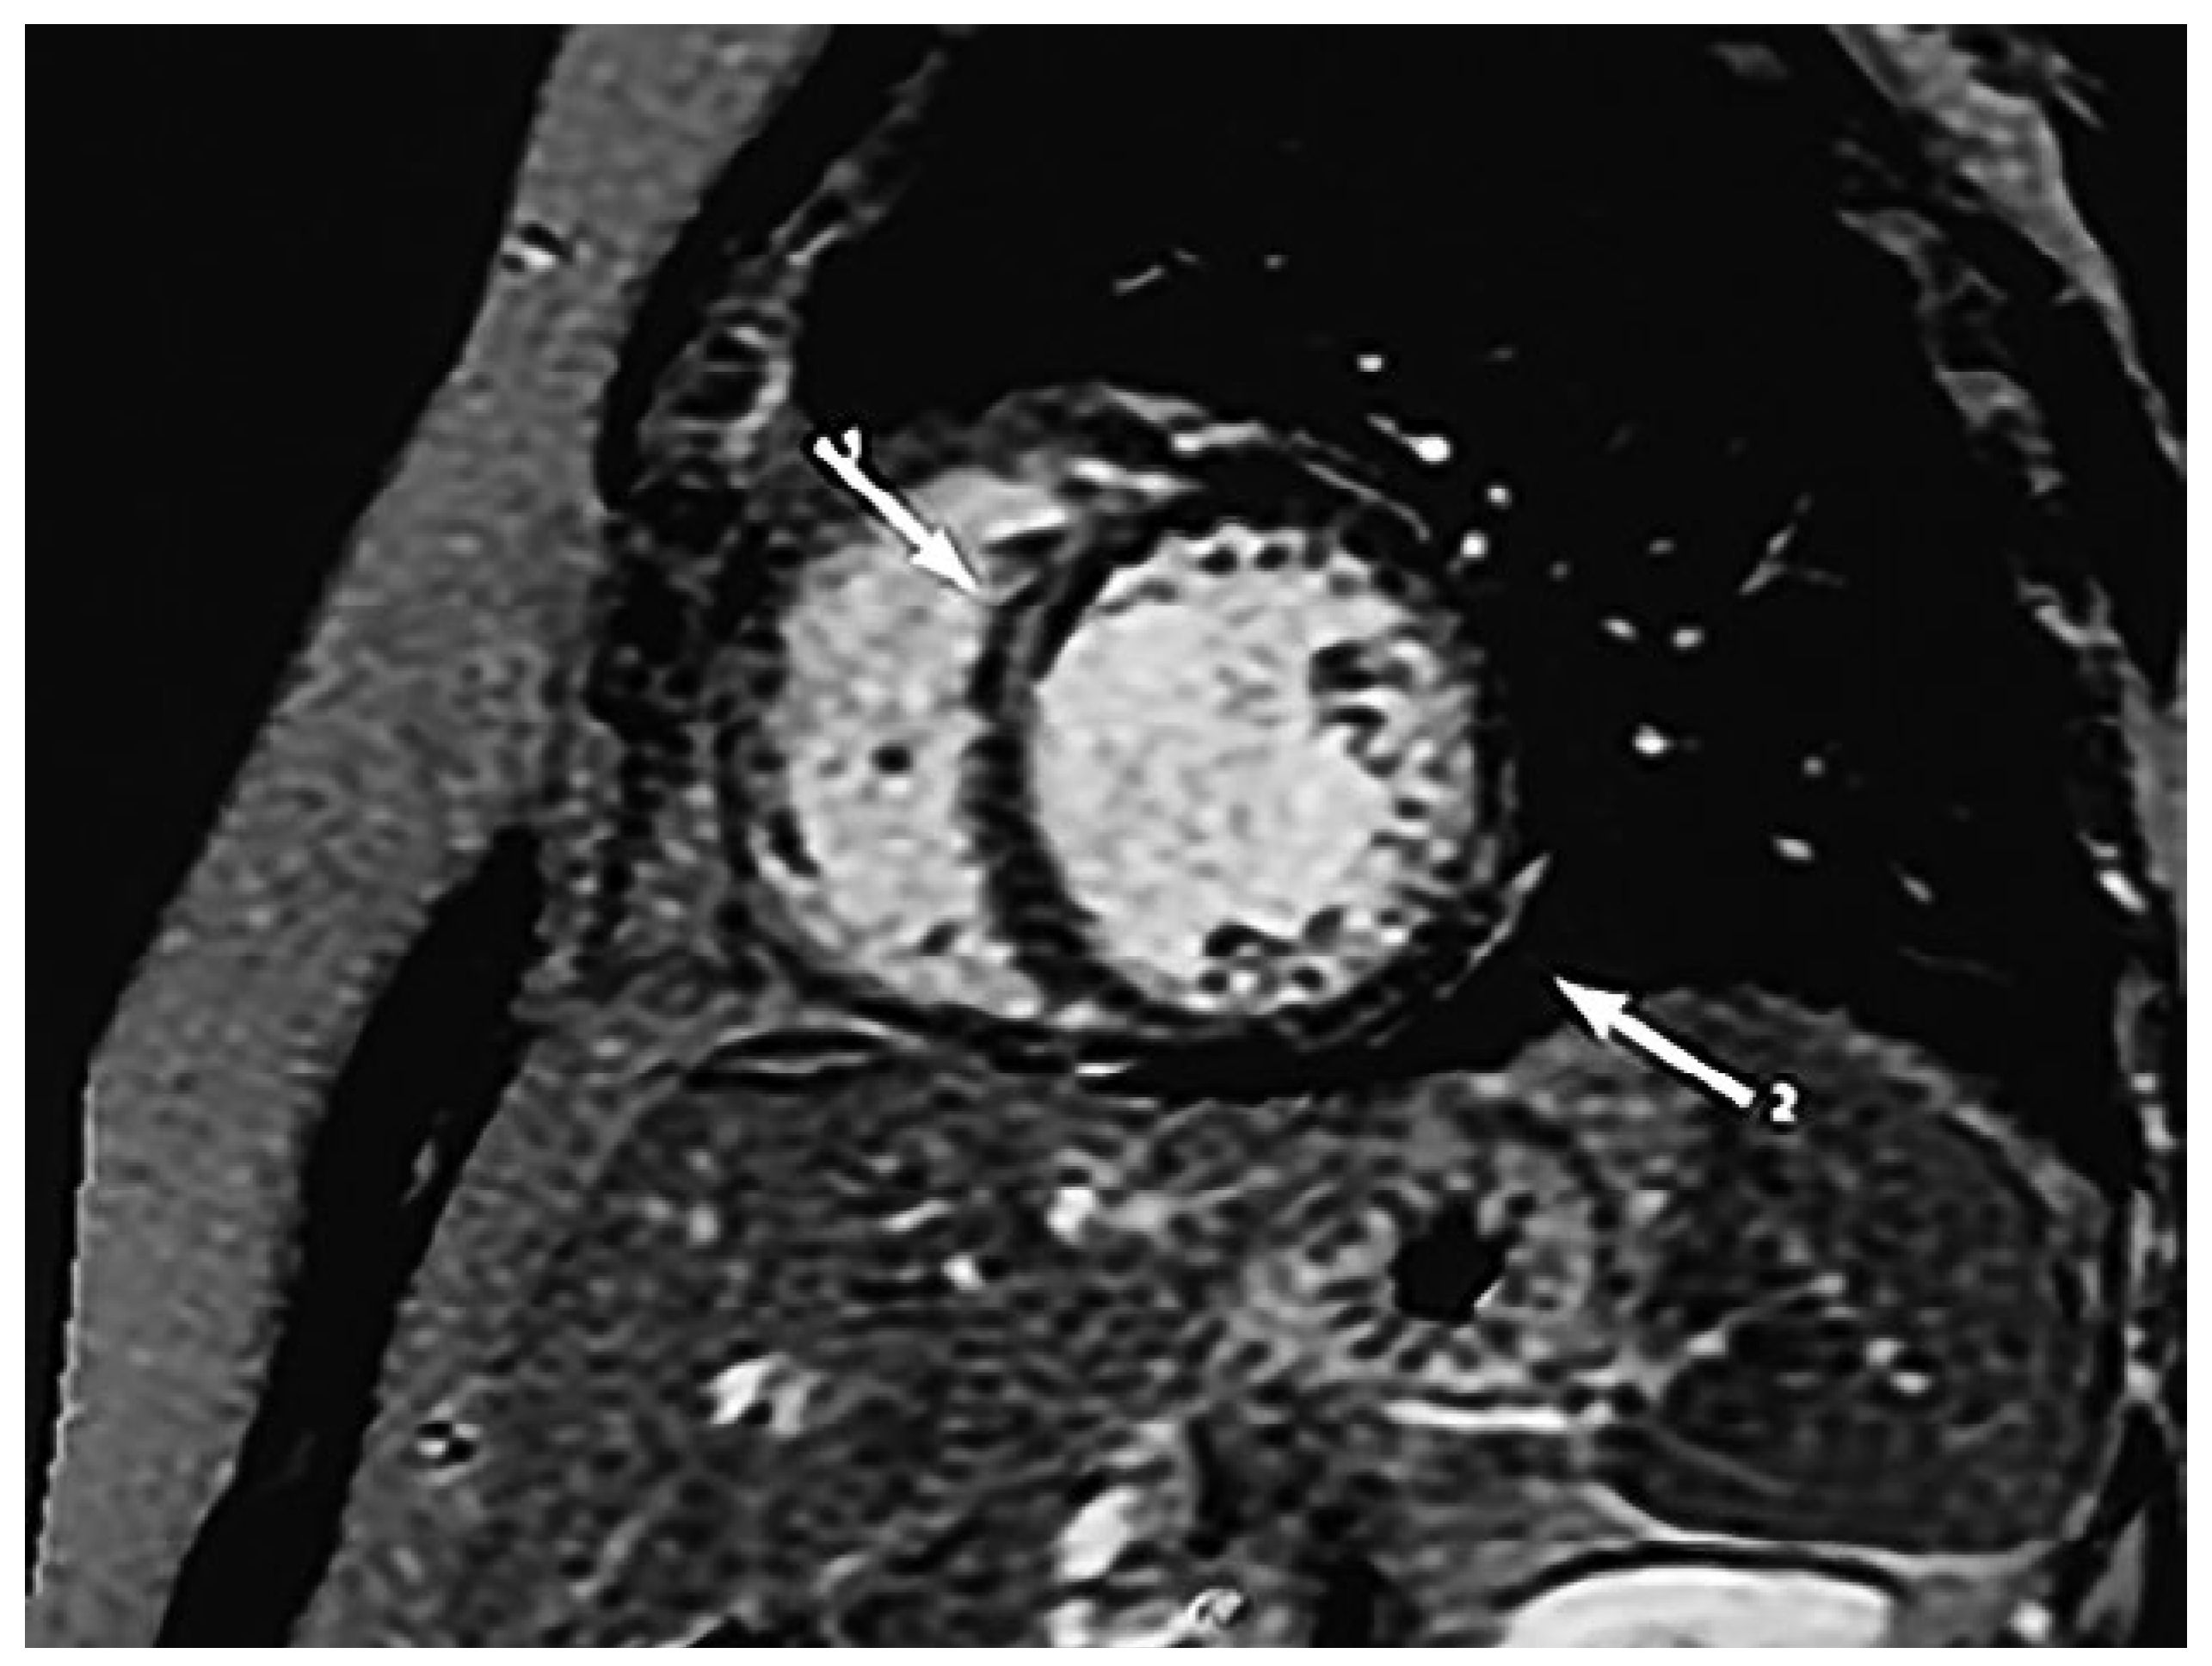

Diagnostic assessment